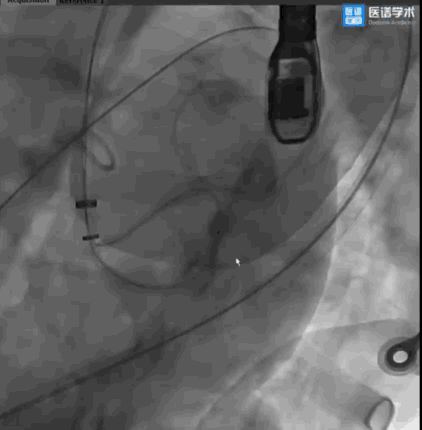

手术采用左侧股动脉入路与右侧股静脉入路,由股动脉入路将环形放置导管输送至瓣下预估并推送出合适角度,在高位开始多角度指引下导丝成环步骤。多学科团队紧密协作,在术前规划的DSA投射体位和梁玉佳教授、魏薪教授的超声引导配合下,术者精细操控,导丝顺利按预期路径环绕二尖瓣瓣叶,导丝成环一次成型,仅耗时30多分钟,建立起固定环植入的重要轨道。

导丝围绕二尖瓣瓣叶成环